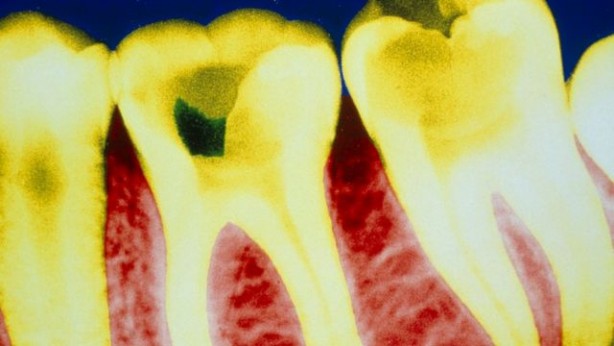

Peki bunu nasıl yapıyor? Diş köküne bir takım uyarı sinyalleri gönderen aspirin, diş yenilenme özelliğini aktif ederek bozuk dişleri onarma, sağlam dişleri ise daha sağlıklı hale getiriyor.

Dişlerin Yenilenmesinde Büyük Rol Oynuyor! Genelde diş çürümesinde kullanılan tedavi bellidir çürük çok ilerlememişse dolgu yapılır, çürük ileri seviyedeyse kanal tedavisi ile diş kurtarılmaya çalışılır. Diş kanal tedavisi ile de kurtarılmıyorsa dişin çekilmesi gibi bir durum ortaya çıkabilir. Prof. Ikhlas El Karim, Queen’s Üniversitesinde yaptığı araştırmalar ile kendinden sıkça söz ettiriyor. Biyomedikal bilimler başkanı olan El Karim, aspirinin diş dolgusu yerini alabilecek bir yapıda olduğunu bu konudaki araştırma sonucunda dolgu olmadan dişleri eski sağlığına döndürebilmenin mümkün olduğundan söz ediyor.

Diş kökünde bulunan hücreleri arttırabilmek dişin çürük dokusunun eski haline gelmesini sağlıyor ve aspirin bu noktada diş kökünde bulunan hücrelerin çoğalması için çok etkili öneme sahip. Anladığımız üzere, aspirin hücre yenilenmesinde etkili peki baş ağrımıza iyi gelmesinin sebeplerinden biri de hücreleri yeniliyor olması olabilir mi? Aspirin diş sağlığı endüstrisi hakkında çok ciddi tasarrufları da beraberinde getirebilir. Profesör El Karim, eczacılar ile ortak yapacakları çalışma ile bu tedaviyi daha hızlı bir şekilde hayata geçireceğine inanıyor. Gelecekte aspirin dolgunun yerini alır mı ya da dolgu diye bir teknoloji kalır mı bunu hep beraber göreceğiz.